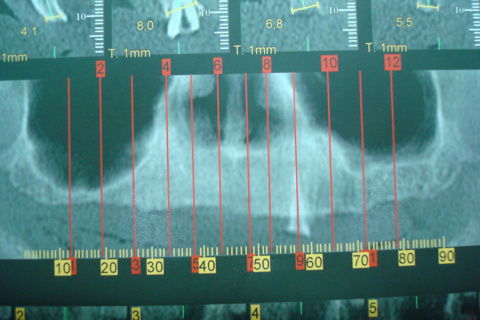

Tomografa pré-operatória